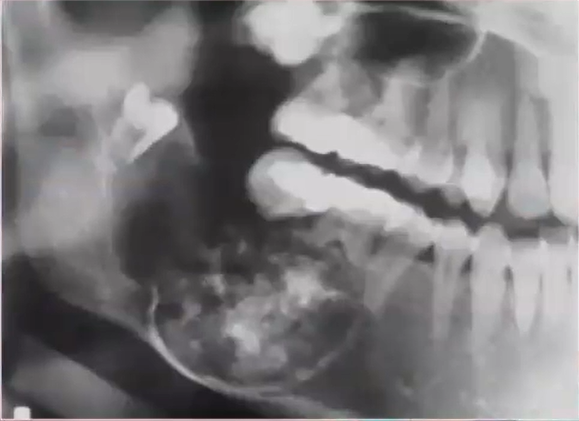

how would you describe this lesions:

ground glass

unilocular

cotton wool

multilocular

multilocular

dx:

osteopetrosis

osteoporotic bone marrow defect

osteoma

condensing osteitis

osteoporotic bone marrow defect